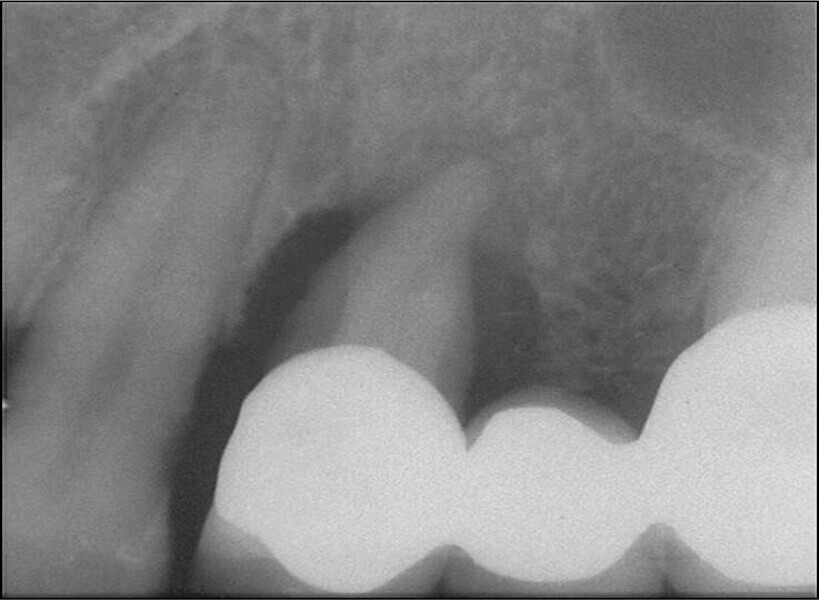

Buccal root of the bifurcated maxillary premolar—a danger zone during root canal therapy